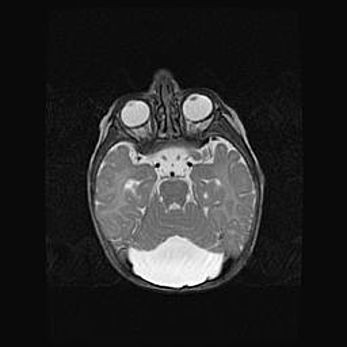

Мальформация Денди-Уокера. Киста задней черепной ямки.

Агенезия мозолистого тела.

Возраст: 2,5 месяца

Вес: 2420 г

Пол: женский

Окружность головы: 37 см

Срок гестации: 32 недели

Мальформация Денди—Уокера — редкий вид патологии ЦНС, представляющий собой врожденный порок развития каудального отдела ствола и червя мозжечка, ведущий к неполному раскрытию срединной (Мажанди) и латеральных (Лушка) апертур IV желудочка мозга. Для этогно синдрома характерна триада симптомов: гипотрофия червя мозжечка и/или полушарий мозжечка, кисты задней черепной ямки, гидроцефалия различной степени. В 70% случаев порок сочетается и с другими аномалиями головного мозга, в частности с агенезией мозолистого тела.